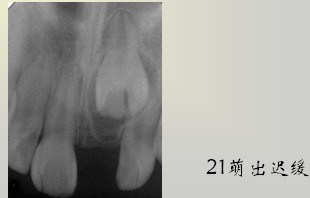

牙齿发育时期受到障碍(遗传、环境、全身、局部)而引起牙齿的数目、形态和组织结构改变,超出了正常范围者称为牙齿发育异常。 数目异常包括:额外牙、缺额牙(先天缺牙)、个别牙缺失或部分牙缺失、无牙症。额外牙的病因不明确,牙源性上皮活性亢进;牙板上皮过度增殖;发育缺陷(颅骨锁骨发育不全、腭裂);遗传、家族性。额外牙 Supernumerary teeth的临床表现:发生率1-3%,乳牙列少见。好发部位:上前牙区(98.3%),最常见上中切牙之间。形态:锥形,,不规则形、与正常牙相似。性别差异:男性多于女性。萌出,或阻生于颌骨内。

额外牙对牙列的影响:恒牙的发育和萌出、牙间隙、牙齿移位、邻牙扭转、邻牙牙根吸收与正常牙融合、恒牙迟萌或阻生 — 含牙囊肿和美观。I其治疗包括:早期发现,适时拔除,及时拔除萌出的多生牙;择期拔除阻生的多生牙,以不影响正常牙发育为原则;埋伏无病变的多生牙,需要定期观察;可替代正常牙的多生牙应予保留。